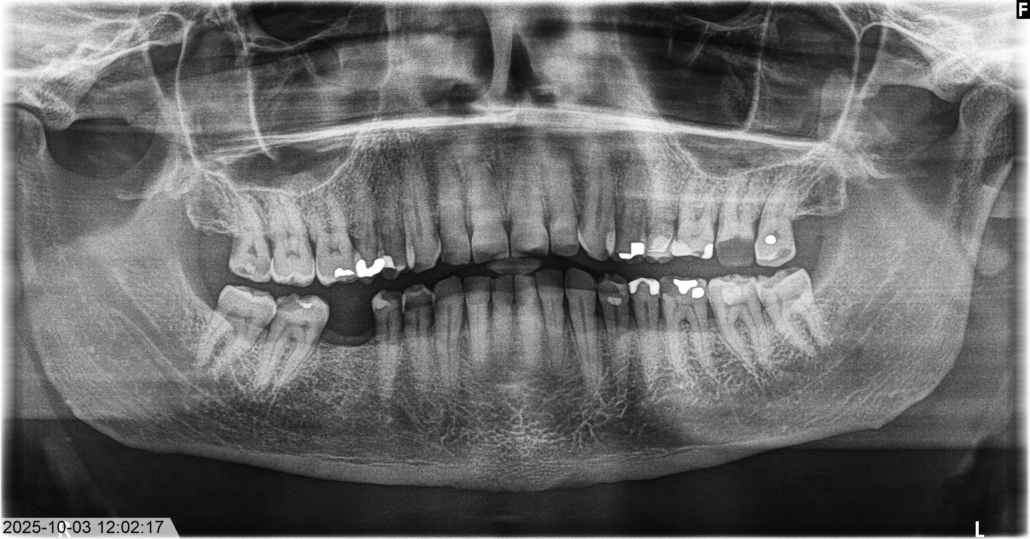

Panorama röntgen (OPG):

En mer omfattande röntgenundersökning där hela bettet avbildas med omgivande strukturer i en enda bild. Används för större terapiplaneringar för att få en helhetsbild.

Panorama röntgen (OPG)